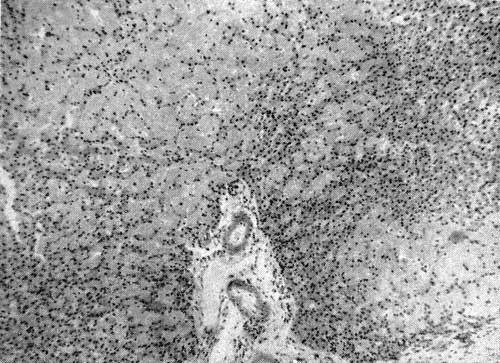

Отложение амилоида в ткани печени (X 90)

Гистологическим исследованием печени у 8 наблюдавшихся нами детей (у 5 на вскрытии и у 3 при биопсии) в качестве преобладающих патоморфологических находок выявлено амилоидное и белково-липоидное перерождение ткани печени.